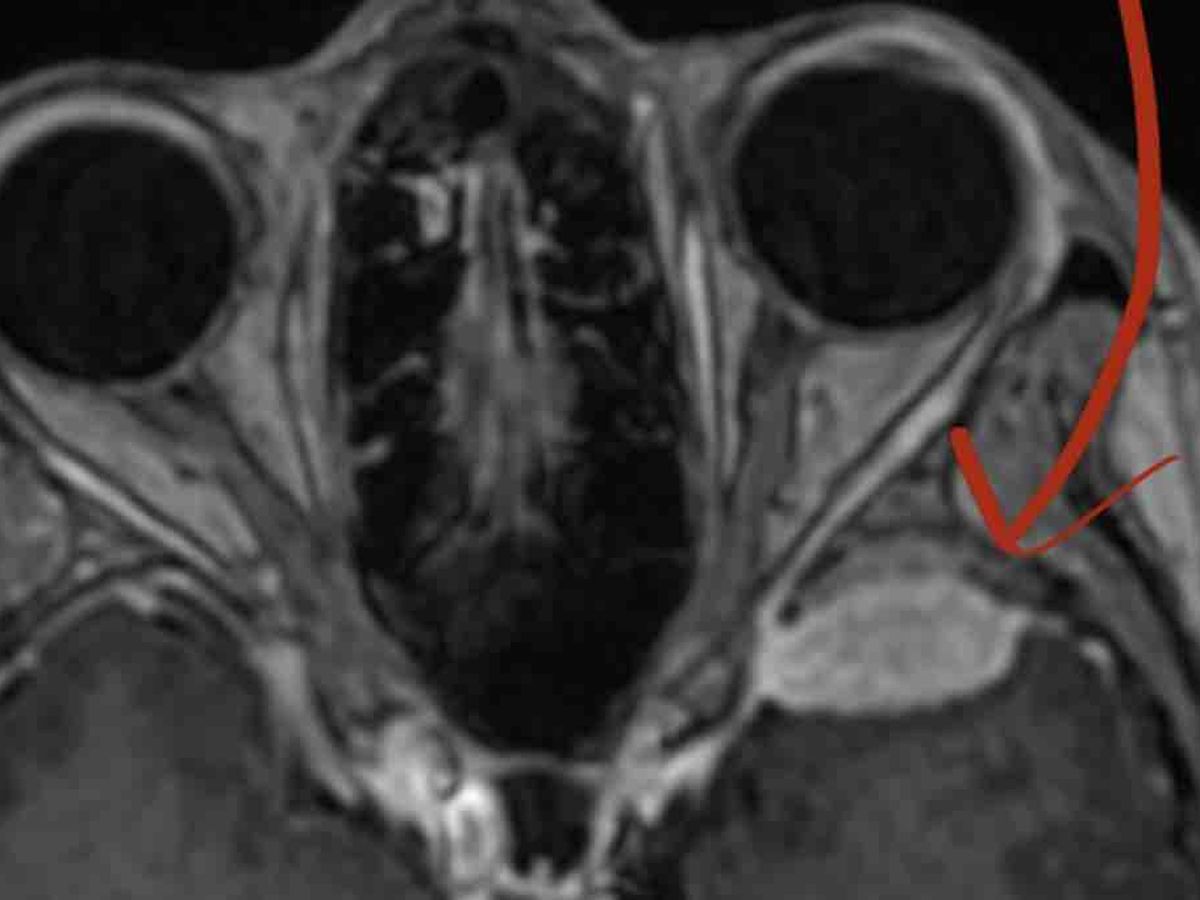

My name is Mimi and I need urgent help. I am 60yrs old, single, living and often struggling with TBI-related brain issues from aneurysm surgery at 45, PEs, strokes, TIAs and chronic illness (Blood clot disorder, POTS, MCAS) and a brain tumor (meningioma). I have other ongoing issues that require medical care so I relocated 5 months ago to be near my family and medical care.

Within the last 4 weeks was I was not only diagnosed  another brain artery anomaly but in addition the brain tumor has doubled in size and is now pressing on part of my brain. Both require intervention. I will have to have cyberknife knife (radiation) surgery  for the brain tumor and brain surgery to the aneurysm.